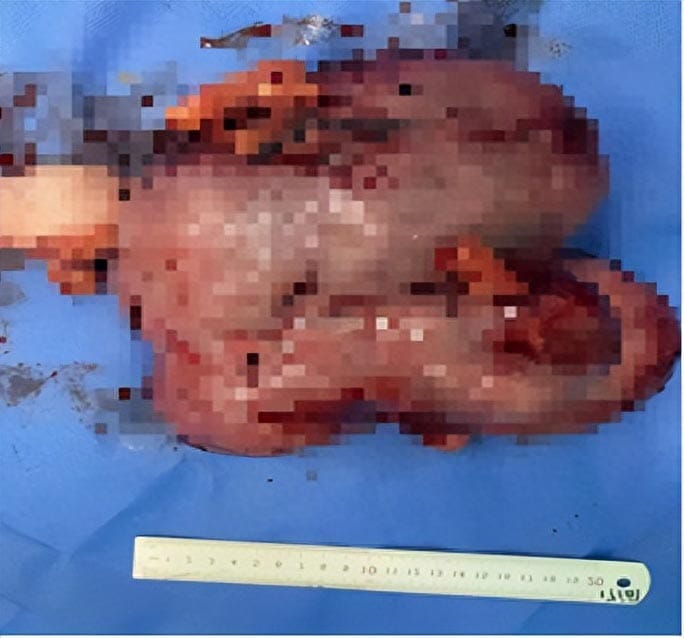

盆腔CT

今年32岁的廖女士2个月前自觉腹部增大,如孕6+月大小,并伴有进行性腹痛腹胀,逐渐加重,慕名到我院就诊。入院后检查,CT显示盆腹腔巨大包块已达19x20cm大小,包块巨大,且性质不明确,加之患者肥胖,贫血、有多次手术史,估计手术难度较大。